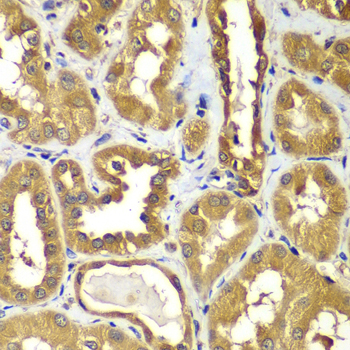

• A7514: image 2

Immunohistochemistry of paraffin-embedded human kidney using RAB1B antibody at dilution of 1:100 (x400 lens).